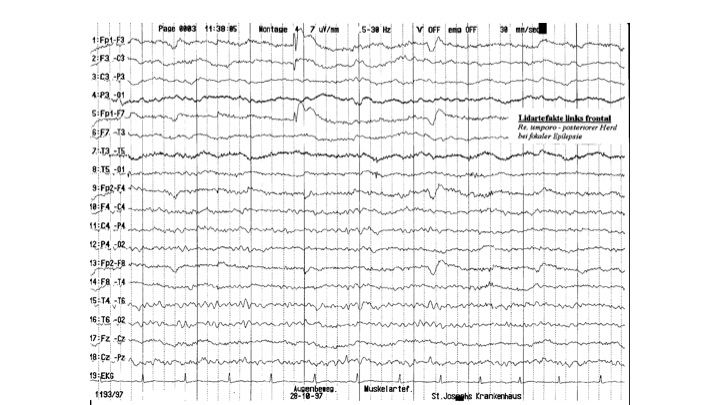

Artefakte im EEG | 11.65 zurück | weiter